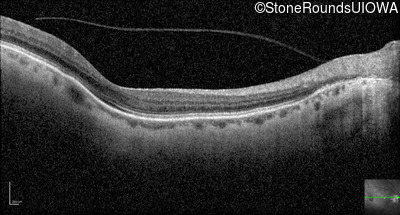

Optical Coherence Tomography - Right - 20/100 -1

Exemplar / OCT Stack

OCT Stack